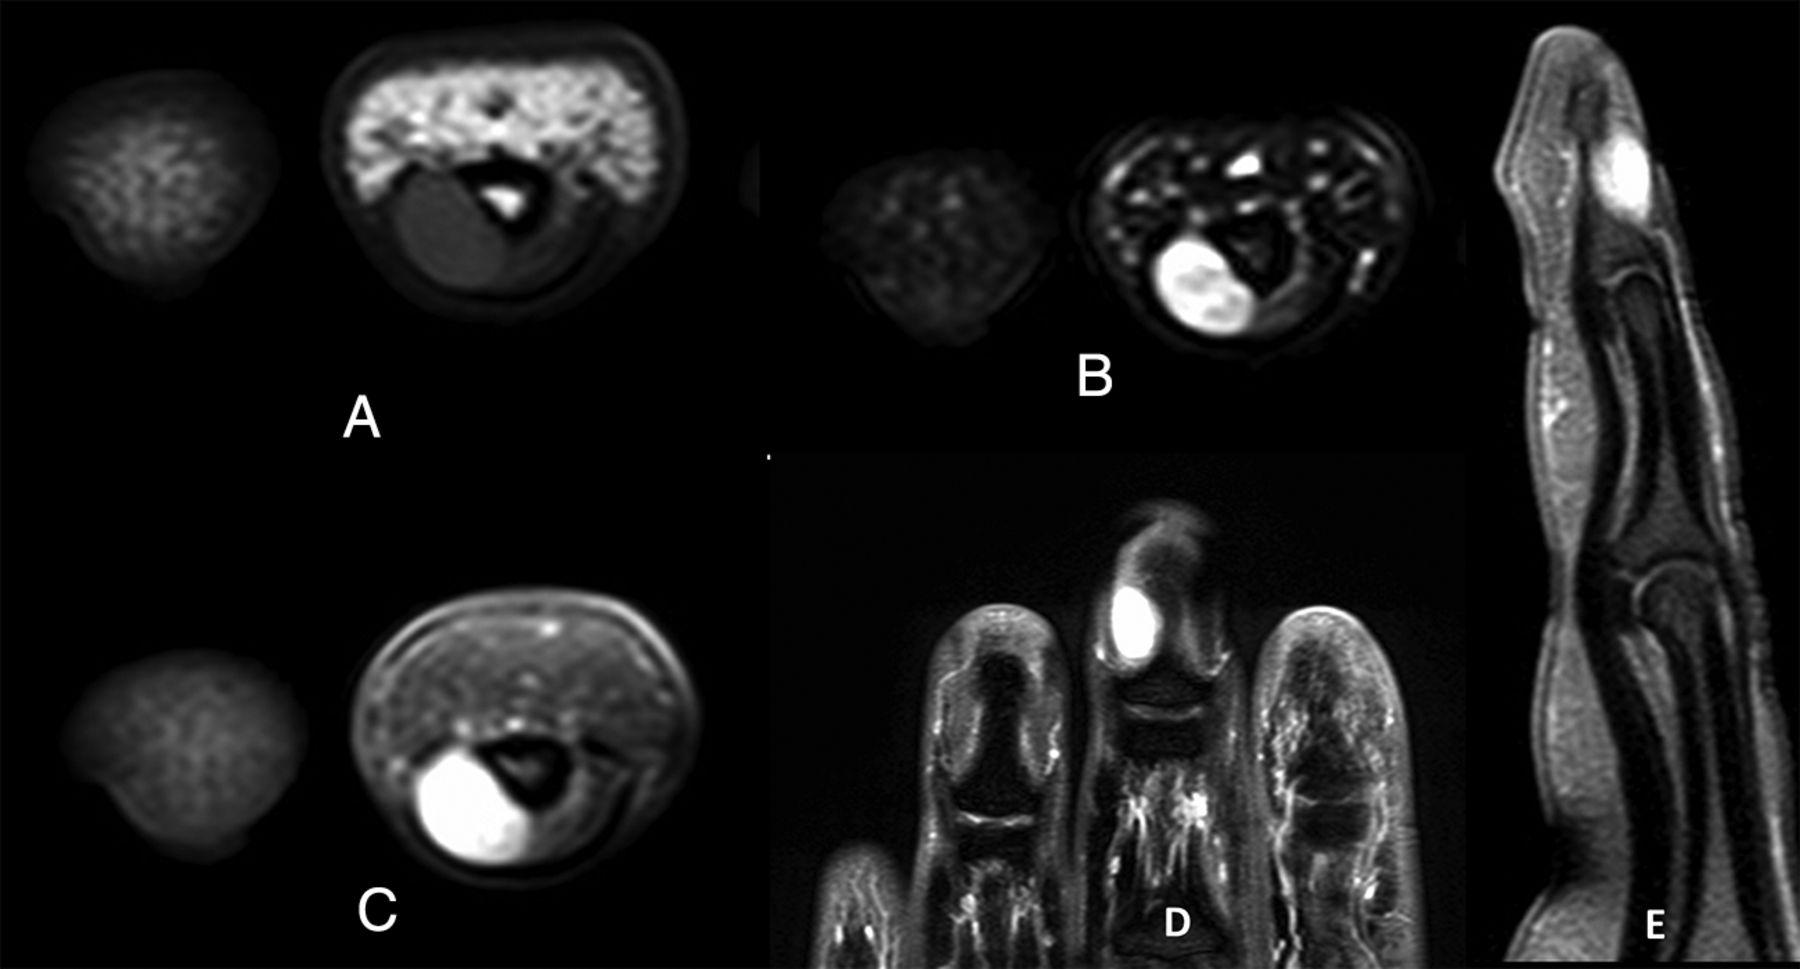

臨床上,甲床內的血管球瘤,在指甲下或呈紫藍色,但通常也難以察覺。倘若以筆尖擠壓患處,痛楚卻會一觸即發。因腫瘤對相連組織構成長期壓力,位於上方的指甲或已出現變形,而位於下方的指骨,在X光下亦會呈現被侵蝕的痕跡。然而磁力共振是最準確的診斷,可發現細至2毫米的血管球瘤。手術切除乃最佳的治療方案,一般可以在局部麻醉下透過顯微鏡徹底切除,術後不但與痛楚告別,再生的指甲亦不再變形。